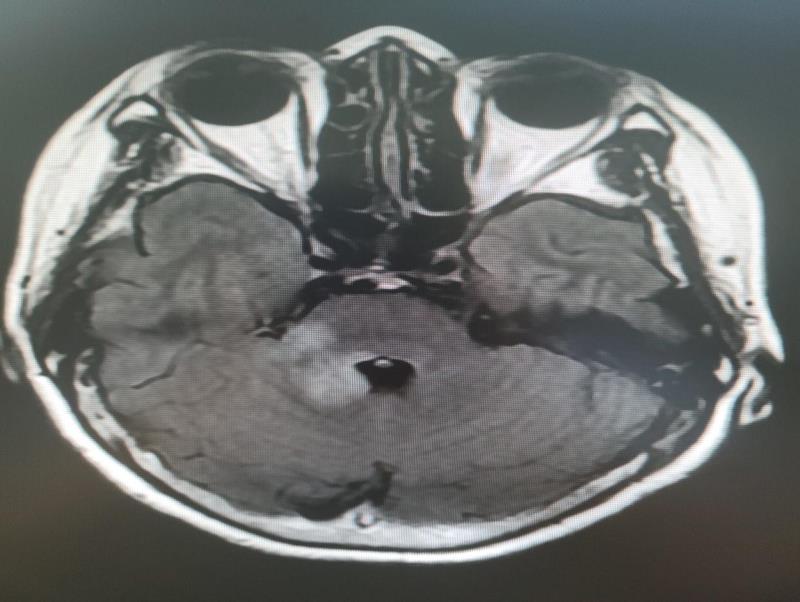

病因找到了!—脑桥右份及小脑蚓部异常信号,考虑缺血缺氧性脑病可能。